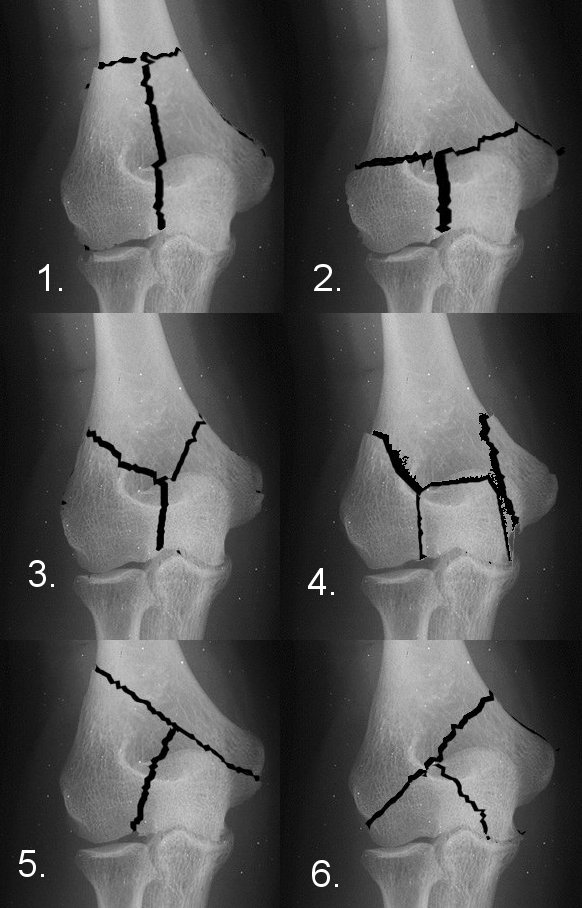

8 Classification of fractures of the distal humerus.a AO classification Classification Of Distal Humerus Fractures Distal humerus fractures are traumatic injuries to the elbow that comprise of supracondylar fractures, single column fractures, column fractures or coronal shear fractures. The ao/ota classification of distal humeral fractures is one of the most frequently used systems for classifying distal humeral fracture s. This review will cover the anatomy and classification of distal humerus fractures, investigations and the treatment. Classification Of Distal Humerus Fractures.